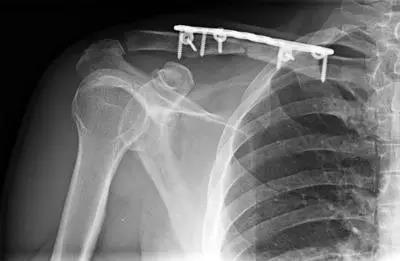

谁知,他的理发技术太好,很多顾客都要求他亲自操剪刀,耐不住顾客们的强烈要求,终于尝试着剪一两个,他感觉特别好,觉得一点不舒服都没有。是也就干脆整天干起活来了,手术后25天左右,那天他送走最后一个顾客,上楼的时候,突然感觉大腿一疼,觉得不对劲。第二天来找我复查,钢板弯曲了,当然,骨折的地方也弯曲了,我说重新手术。

听到这个消息,理发师吃惊极了,又骨折了?连钢板也弯了?对于一个普通人来说这简直是不可思议,难道是钢板有质量问题?再次手术无论对身体和心情,经济都是一个打击,将来是不是会有残疾啊?

体内钢板的断裂学名钢板疲劳性断裂,是指在骨折部位未达到骨性愈合时,不能够承载重力,本来应由骨头承担的体重全部转移给了钢板,钢板承担了长期的慢性的弯曲、旋转应力,导致钢板局部的分子构型发生变化,使钢板局部承担应力的能力逐渐下降,当钢板的承载力低于体重产生的应力时,最终会导致钢板断裂。

你自己用一把薄一些的调羹,反复折弯,慢慢的,调羹会折断。钢板也一样,如果骨折还没愈合,钢板被身体的重量反复挤压,千次万次,终究会疲劳,并断裂。

钢板断裂是骨折术后的一种并发症,如果骨折术后过早活动,还没长好的骨头不能承担病人自身的重量,重量自然会被钢板承担,如果这种应力效应在几个月的时间不断作用于钢板,钢板就很会疲劳性断裂。